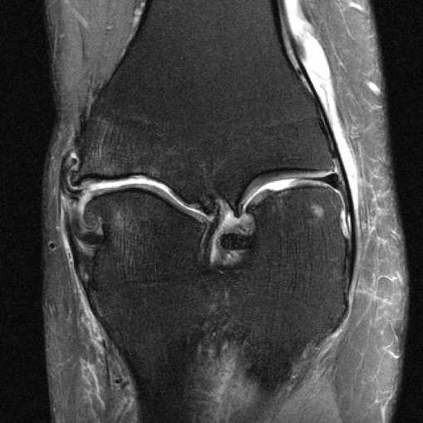

Deep Learning (DL) methods have shown promising results for solving ill-posed inverse problems such as MR image reconstruction from undersampled $k$-space data. However, these approaches currently have no guarantees for reconstruction quality and the reliability of such algorithms is only poorly understood. Adversarial attacks offer a valuable tool to understand possible failure modes and worst case performance of DL-based reconstruction algorithms. In this paper we describe adversarial attacks on multi-coil $k$-space measurements and evaluate them on the recently proposed E2E-VarNet and a simpler UNet-based model. In contrast to prior work, the attacks are targeted to specifically alter diagnostically relevant regions. Using two realistic attack models (adversarial $k$-space noise and adversarial rotations) we are able to show that current state-of-the-art DL-based reconstruction algorithms are indeed sensitive to such perturbations to a degree where relevant diagnostic information may be lost. Surprisingly, in our experiments the UNet and the more sophisticated E2E-VarNet were similarly sensitive to such attacks. Our findings add further to the evidence that caution must be exercised as DL-based methods move closer to clinical practice.